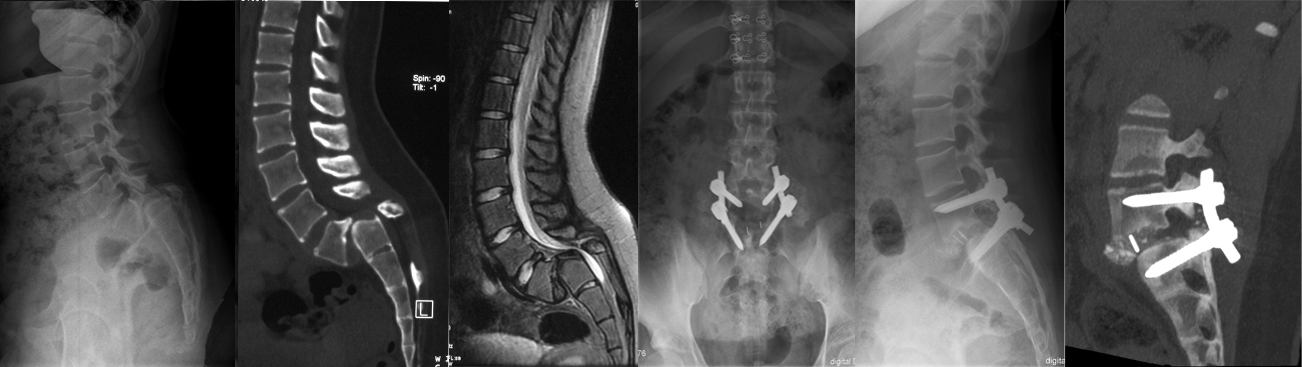

某男,57岁,强直型脊柱炎胸腰段后凸畸形,双下肢无力伴大小便功能障碍.单纯后路前方张开后方闭合截骨矫形术

男,L1陈旧骨折后凸畸形,下肢不全瘫,,单纯后路经椎间隙闭合截骨矫形

后路畸形节段截骨矫形固定,前路椎间植骨融合术,术前屈:85度、伸105度,术后30度

后路畸形节段截骨矫形固定,前路椎间植骨融合术,术前94度、术后52度